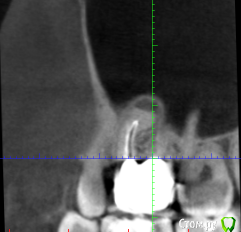

Техник глядя на снимок сказала что над шестерками гранулема (если я правильно запомнил термин). Корни торчат в пазухи.

По снимку стало ясно, что на шестерках не пролечено по каналу (как раз над тем где воспаление) а еще не пройден один до конца.

Выяснилось что те каналы, что пройдены - пройдены резорцин-формалином (если правильно запомнил название), то есть хрен распломбируешь.

Периодические воспаления носовой полости с левой(по направлению моего взгляда) стороны. Зуб шестерку я натурально чувствую, не как живой зуб, ничего не больно, а как будто что-то внутри зубной лунки почесывается/раздражено. С правой стороны такого нет, хотя похожая ситуация. По ощущениям обостряется когда ем сладкое, соответственно почти бросил. Нюх только с правой стороны остался. Когда воспаляется общее состояние угнетенное.

1) Картинки (не знаю тот ли кусок но воспаление вроде бы видно ) по возможности уменьшил размер, прикрепил к сообщению. Если нужно будет другие - подскажите, сделаю.